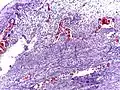

Pathology diagnosis of appendicitis can be made by detecting a neutrophilic infiltrate of the muscularis propria.

Micrograph of appendicitis and periappendicitis. H&E stain

Micrograph of appendicitis showing neutrophils in the muscularis propria. H&E stain

Acute suppurative appendicitis with perforation (at right). H&E stain